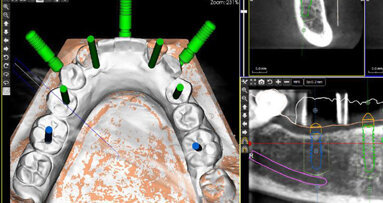

Tvoření chirurgické šablony na základě naplánované pozice implantátu v programu SIMPLANT.

Spojení CBCT snímku, skenu CEREC a plánované pozice implantátu.

Naplánovali jsme jednodobou implantaci s okamžitou tzv. nefunkční korunkovou rekonstrukcí, bez okluzních kontaktů. Zhotovili jsme CBCT vyšetření a dále jsme s pomocí skeneru CEREC Omnicam naskenovali horní i dolní zubní oblouk, a také tzv. buccal scan. Skeny jsme dále odeslali formou souborů STL a se soubory DICOM byly složeny v programu SIMPLANT. V souladu s pravidlem 3A-2B (F. Rojas-Vizcaya) byla naplánována optimální poloha implantátu ANKYLOS C/X B 14, využívající možnosti programu SIMPLANT.

Intraorální sken umožnil zakreslení budoucí protetické rekonstrukce tak, aby bylo možno zhotovit šroubovanou korunku. Bylo to důležité obzvláště ve snaze předejít tzv. cementitis – zánětu vyvolanému cementem.